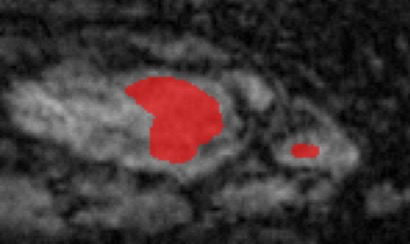

Medical data often exhibits long-tail distributions with heavy class imbalance, which naturally leads to difficulty in classifying the minority classes (i.e., boundary regions or rare objects). Recent work has significantly improved semi-supervised medical image segmentation in long-tailed scenarios by equipping them with unsupervised contrastive criteria. However, it remains unclear how well they will perform in the labeled portion of data where class distribution is also highly imbalanced. In this work, we present ACTION++, an improved contrastive learning framework with adaptive anatomical contrast for semi-supervised medical segmentation. Specifically, we propose an adaptive supervised contrastive loss, where we first compute the optimal locations of class centers uniformly distributed on the embedding space (i.e., off-line), and then perform online contrastive matching training by encouraging different class features to adaptively match these distinct and uniformly distributed class centers. Moreover, we argue that blindly adopting a constant temperature $\tau$ in the contrastive loss on long-tailed medical data is not optimal, and propose to use a dynamic $\tau$ via a simple cosine schedule to yield better separation between majority and minority classes. Empirically, we evaluate ACTION++ on ACDC and LA benchmarks and show that it achieves state-of-the-art across two semi-supervised settings. Theoretically, we analyze the performance of adaptive anatomical contrast and confirm its superiority in label efficiency.

翻译:医学数据经常呈现长尾分布和重度类别不平衡,这自然导致在对少数类别(即边界区域或罕见目标)进行分类时出现困难。最近的研究在长尾情况下通过装备医学影像的无监督对比标准,明显改进了半监督医学图像分割。然而,在标记的数据部分中,类别分布也极为不平衡,因此它们的表现如何仍不清楚。在本研究中,我们介绍一种采用自适应解剖对比度改进的对半监督医学分割行动的框架(ACTION++)。具体来说,我们提出了一种自适应监督对比损失,它首先在嵌入空间上计算出不同类别的优化位置(即离线),然后通过鼓励不同类别之间的特征与这些不同和均匀分布的类别中心相适应的在线对比匹配训练来进行自适应匹配。此外,我们认为,在长尾医疗数据中盲目采用常温度$\tau$不是最优的,因此通过一个简单的余弦计划来使用动态$\tau$来产生更好的多数类别和少数类别之间的分离。在实证方面,我们在ACDC和LA基准测试中评估ACTION++,并展示了其在两种半监督设置下的最新成果。从理论上讲,我们分析了自适应解剖对比度的性能,并证实了它在标签效率上的优越性。